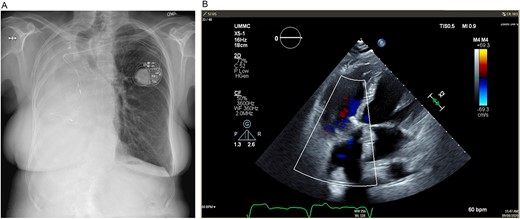

(A) Preoperative posteroanterior view chest X-ray showing left to right mediastinal contents shifted and a clear left lung. (B) Preoperative transesophageal echocardiogram with doppler showing severe tricuspid regurgitation with no coaptation between the anterior and septal leaflets.